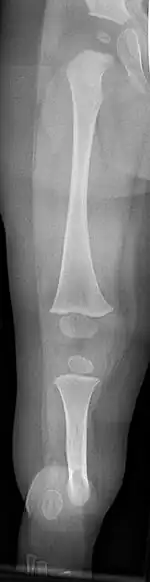

Eine fibulare Hemimelie oder ein fibulärer Längsdefekt ist das angeborene Fehlen (Aplasie) oder die Unterentwicklung (Hypoplasie) des Wadenbeins (Fibula). Sie kann isoliert, häufiger aber in Verbindung mit Fehlbildungen des Oberschenkelknochens (proximaler Femurdefekt), Fehlbildungen am Fuß lateral sowie mit einer Verkürzung des gesamten Unterschenkels vorkommen.[1] Das noch wesentlich seltenere angeborene Fehlen des Schienbeines wird als tibiale Hemimelie bezeichnet.

Eine Hypoplasie oder Aplasie der Fibula ist meist Teil eines Fehlbildungsspektrums mit Veränderungen auch am Knie, Oberschenkel, Schienbein und Fuß.

Funktionell im Vordergrund steht die im Verlauf des Wachstums zunehmende Beinverkürzung, die bis zu 12–18 % der Beinlänge ausmachen kann und fast immer auch mit einer Verkürzung des Oberschenkels einhergeht (Femurhypoplasie).[2][7]

Das Schienbein weicht in der Regel vorn-seitlich ab, besonders stark bei vollständigem Fehlen der Fibula. Am Knie ist oft der laterale Femurkondylus unterentwickelt und es besteht ein Genu valgum (X-Bein).[1][8] Oft fehlt auch das vordere Kreuzband.

Bereits im Mutterleib kann während einer Ultraschalluntersuchung die Fehlbildung erkannt werden,[10] die Verkürzung und Verkrümmung ist nach der Geburt offensichtlich. Ein Röntgenbild kann das Ausmaß der Fehlbildung sowie zusätzliche knöcherne Veränderungen dokumentieren.